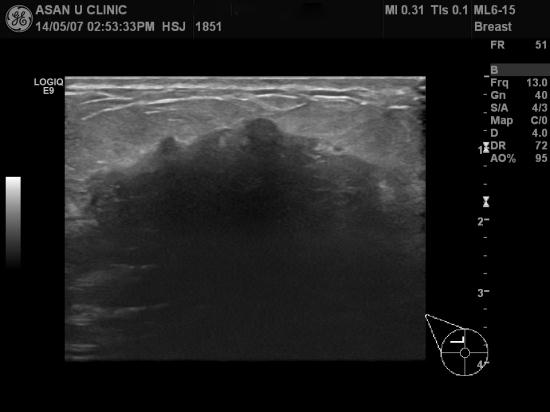

첫아기 수유 4개월경인 37세 여성분으로,

우측 유방에 몽우리가 커져 염증인것으로

생각하다가 통증심해져 내원하셨습니다.

우측유방유두부터 상외측으로 초음파 프르브에 다 안잡힐 정도의

거칠고 불분명한 경계의 저에코 결절이 있었고

겨드랑이 또한 림프절 비대 소견이 동반되어 있습니다.